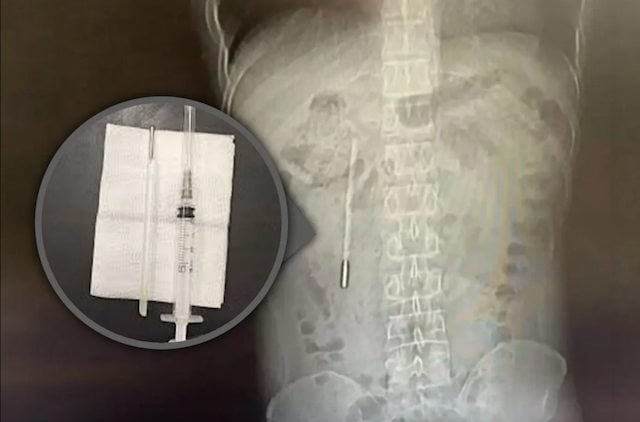

Selon nos confrères, un examen a révélé la présence d'un corps étranger dans son duodénum, c'est-à-dire la partie initiale de l'intestin grêle, que les médecins soupçonnaient fortement d'être un thermomètre à mercure. C'est alors que le patient, comme foudroyé par ce souvenir enfoui, a confirmé l'incident de son enfance.

Crédit Photo : SCMP composite/Weibo

Le hic ? L'extrémité de l'objet appuyait directement contre la paroi intestinale, ce qui signifiait qu'il y avait un risque élevé de perforation et d'hémorragie interne. Sans compter que le mercure contenu dans un thermomètre classique est une substance hautement toxique, susceptible d'empoisonner l'organisme en cas de fuite. Les chirurgiens ont réussi à retirer le corps étranger en seulement 20 minutes, au cours d'une intervention très délicate.

Contre toute attente, le thermomètre récupéré était intact, mais ses graduations avaient été effacées par les années passées dans l'organisme. Ce cas médical n'a pas manqué de choquer la toile. Un internaute a notamment indiqué :